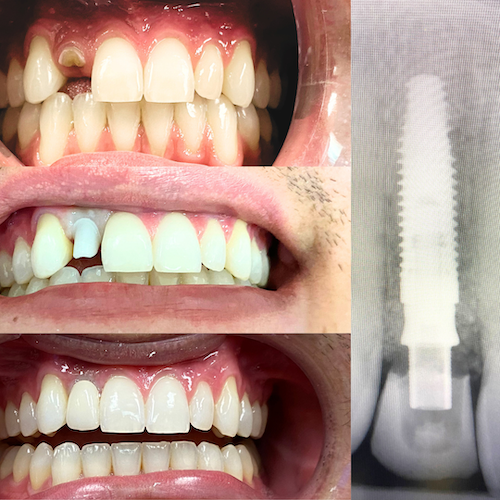

Dental implants replace both the tooth and its root. The implant itself is a small titanium post placed into the jawbone, where it securely anchors a custom restoration.

3. Healing and Integration – Over several weeks to months, the implant integrates with the jawbone in a natural process called osseointegration, creating a strong foundation.

4. Final Restoration – A custom-made crown, bridge, or implant-supported denture is attached, restoring function and aesthetics.